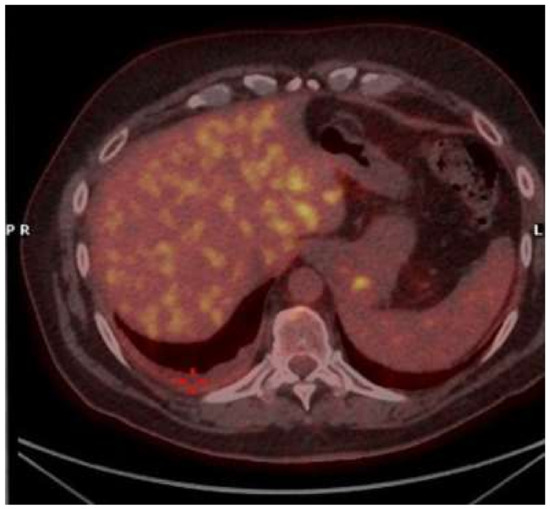

2. Case Presentation